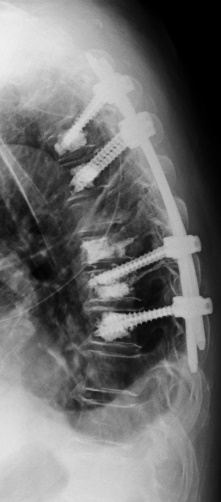

Fehlstellungen der Wirbelsäule können angeboren, im Wachstumsprozess entstanden oder abnutzungsbedingt sein. Dadurch wird die sensible Statik der Wirbelsäule beeinträchtigt, was sich ungünstig auf Muskulatur, Wirbelgelenke, Rippen oder auch auf die inneren Organe auswirken kann. Diese Fehlstellungen können sich in Form einer seitlichen Verkrümmung der Wirbelsäule (Skoliose) zeigen oder in einer Krümmung nach vorn (Kyphose) oder nach hinten (Lordose/Hohlkreuz). In weniger fortgeschrittenen Fällen kommt beispielsweise Physiotherapie oder eine Korsettbehandlung zur Anwendung. Wenn die Fehlstellung durch die Muskulatur nicht mehr ausgeglichen werden kann und zu anhaltenden Schmerzen oder einer Beteiligung der Nerven führt, kann eine korrigierende Versteifungsoperation notwendig werden.

Der Begriff Osteochondrose beinhaltet den Verschleiß eines oder mehrerer Bewegungssegmente der Wirbelsäule. Häufigste Lokalisation ist der Zwischenwirbelraum der unteren Lendenwirbelsäule. Dabei kann es durch den Verschleiß der Bandscheibe zur lokalen Rücken/Nacken-Beschwerden kommen oder durch daraus resultierende Instabilität eine Spinal- oder Nerveneinengung mit ausstrahlenden Beschwerden verursachen. Im fortgeschrittenen Stadium kann dies auch zu ausgeprägten Wirbelsäulenverkrümmungen führen, die dann möglicherweise einen "Ganzwirbelsäulenschmerz" verursachen. Die Therapie der Wahl bei Osteochondrose an der Lendenwirbelsäule ist nach Ausschöpfung der konservativen Therapiemaßnahmen die Spondylodese oder Versteifung. Dabei werden nur die betroffenen Bereiche mit einem Schraubenstabsystem überbrückt und die verschlissenen Bandscheiben durch einen Platzhalter ersetzt.